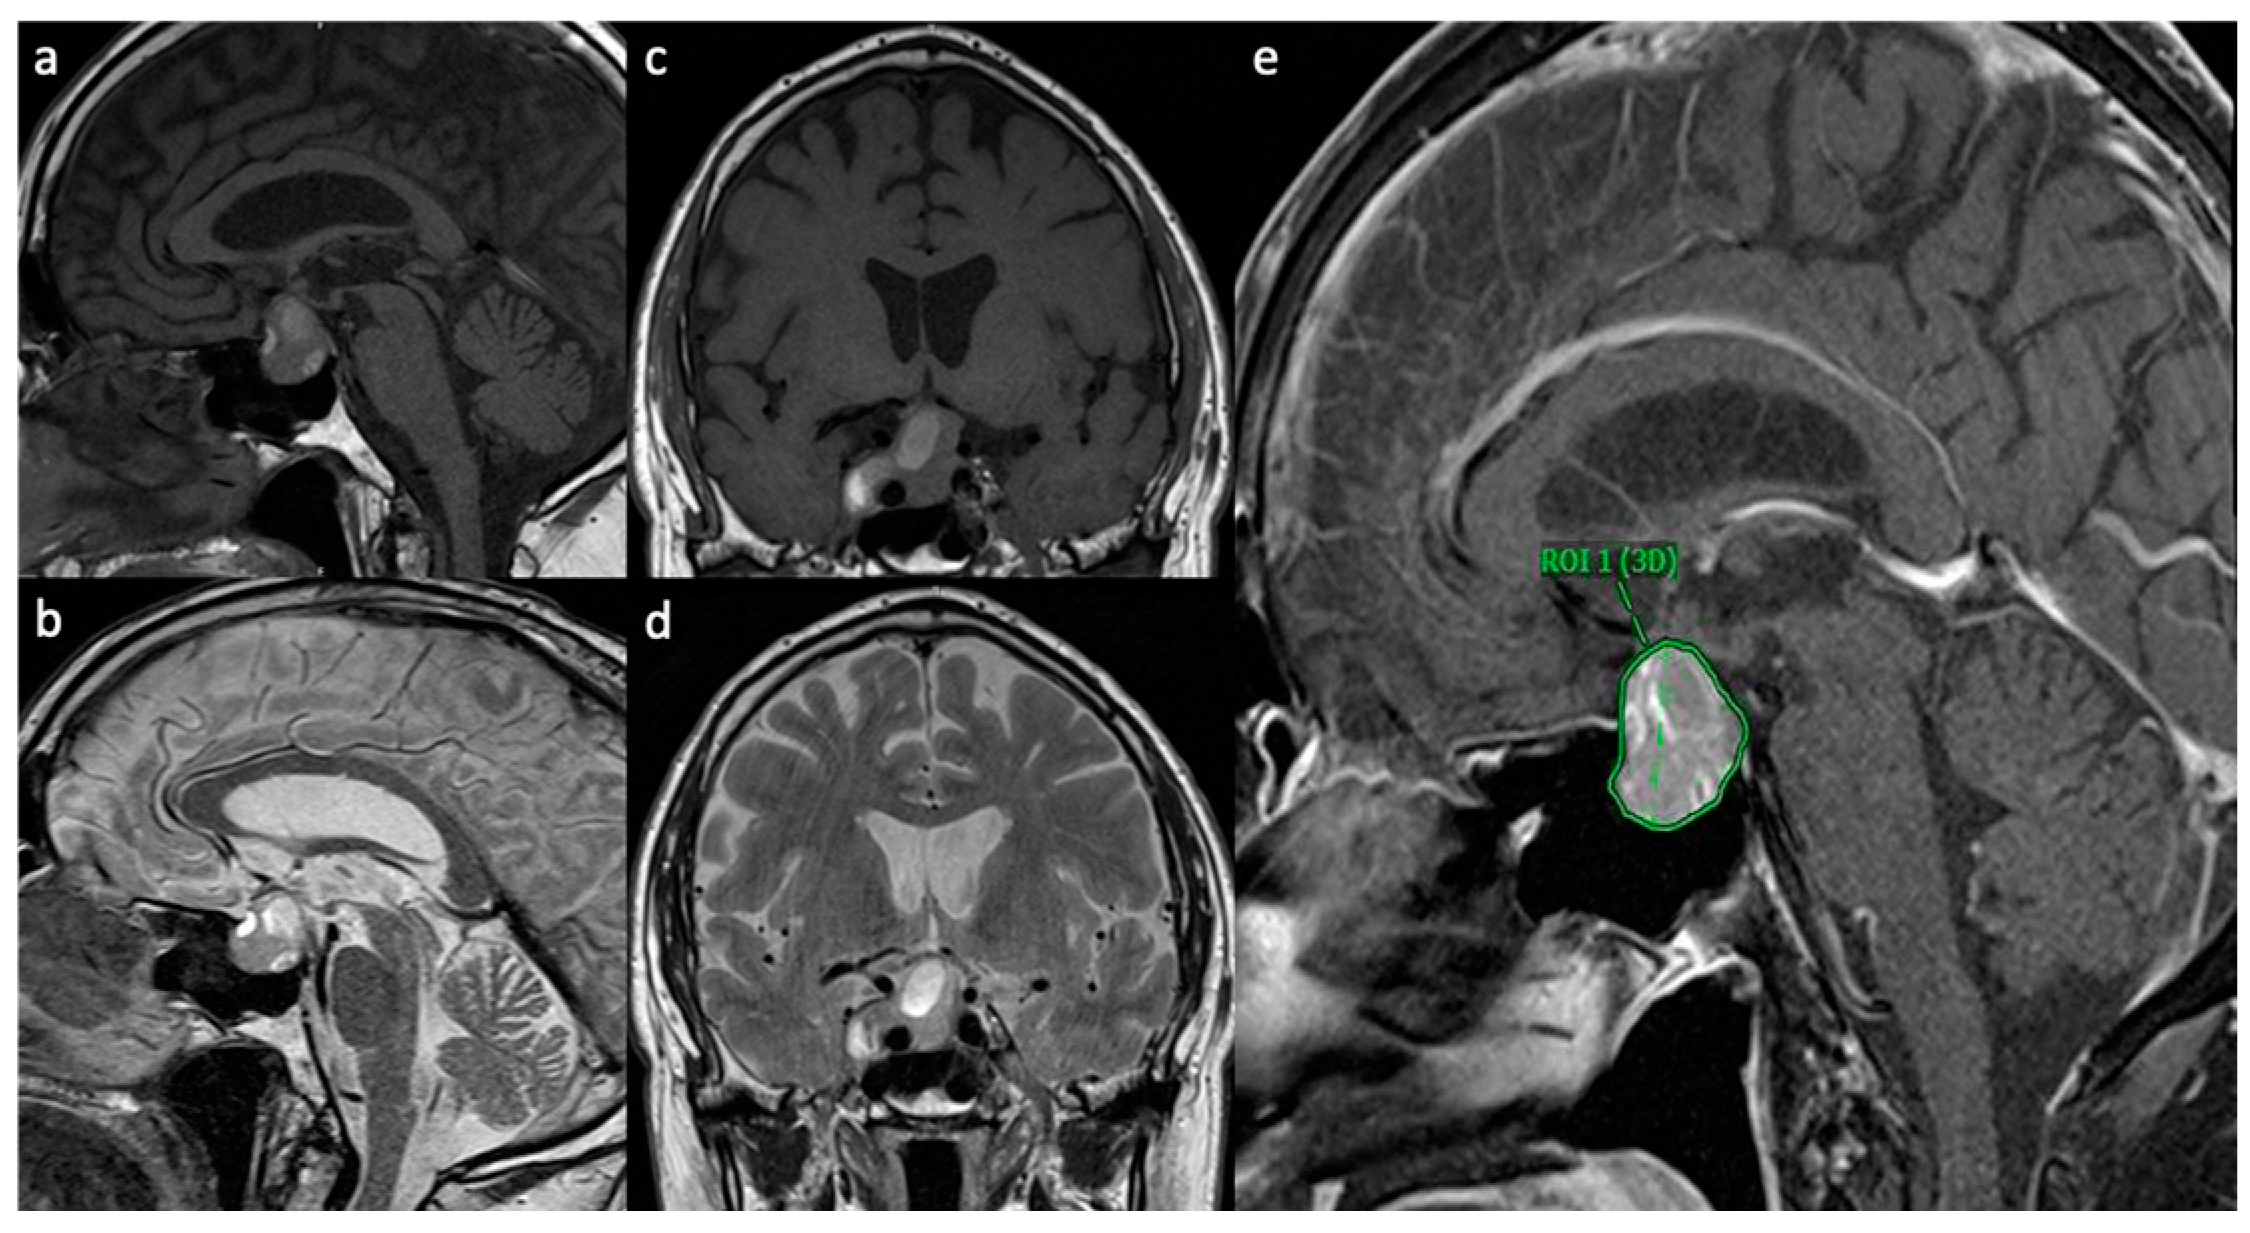

The medical records of a consecutive series of 100 patients who presented with a PitNet at the Department of Neurosurgery of Hannover Medical School between 2017 and 2022 were analyzed retrospectively. The patients were divided into two groups (hemorrhagic PitNet: H-PitNet; and non-hemorrhagic PitNet: NH-PitNet) based on the preoperative MRI findings, neuropathologic findings and clinical presentation. Hemorrhages were identified on non-enhanced T1- and T2-weighted MRI, as described by Wang et al. (see Figure 1) [8].

To identify possible factors associated with hemorrhage, we compared age, sex, BMI, tumor volume, neuropathological findings, smoking status, the presence of arterial hypertension (when previously diagnosed and treated with antihypertensive agents) and of diabetes mellitus between the two groups. The tumor volume was measured using semiautomated 3D-ROI-based volumetry (software: Visage Imaging Inc. ©, V 7.1.18, 2020, San Diego, CA, USA; see Figure 1), as described previously [9].

Figure 1. Representative MRI scans of H-PitNet with multiple hemorrhagic lesions. (a) Sagittal T1W MRI showing T1 hyperintense hemorrhagic lesions in a PitNet; (b) sagittal MRI showing T2 hyperintense lesions in a PitNet. The same lesions are displayed in the coronal view in (c) (T1W) und (d) (T2W). A sagittal view of contrast-enhanced T1W MRI is displayed in (e), showing an inhomogeneous contrast enhancement on the PitNet, which is marked as a 3D region of interest (ROI) for volumetry.